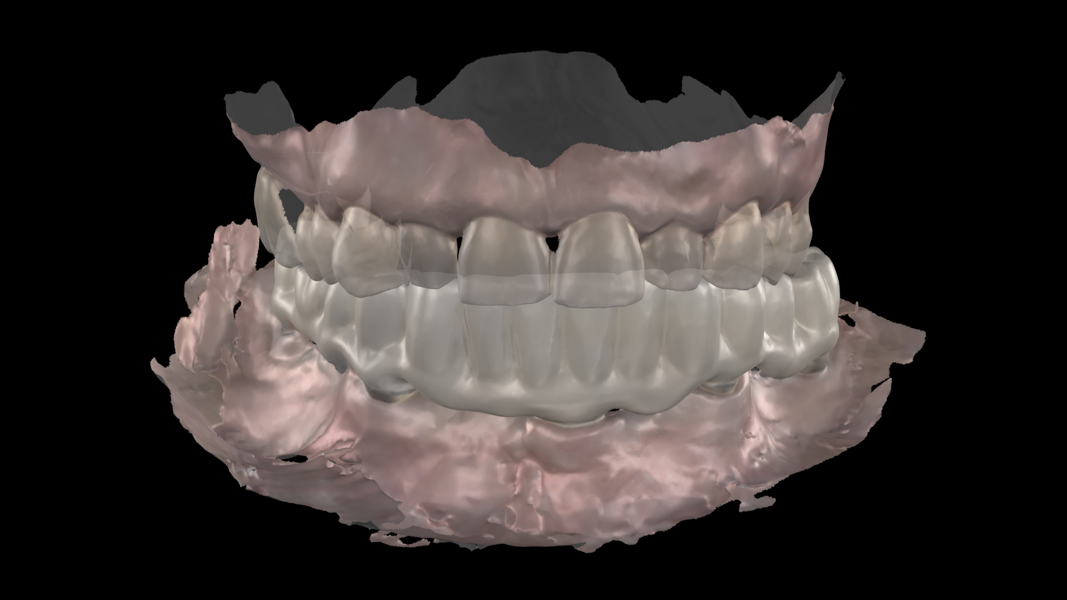

Figs. 2a & b: Intra-oral scans of the pre-op situation.

Intra-oral examination revealed compromised mandibular dentition, an old fixed prothesis, missing posterior teeth on the left side, periodontal involvement and gingival inflammation. A panoramic radiograph was obtained, and the findings were reported to the patient (Figs. 1a & b; 2a & b). Both mandibular canines had visible periapical radiolucencies. A CBCT scan was performed for a more detailed assessment of the alveolar bone anatomy (Figs. 3a & b). Temporomandibular joint examination revealed no indication of dysfunction (crepitus, clicking or pain).